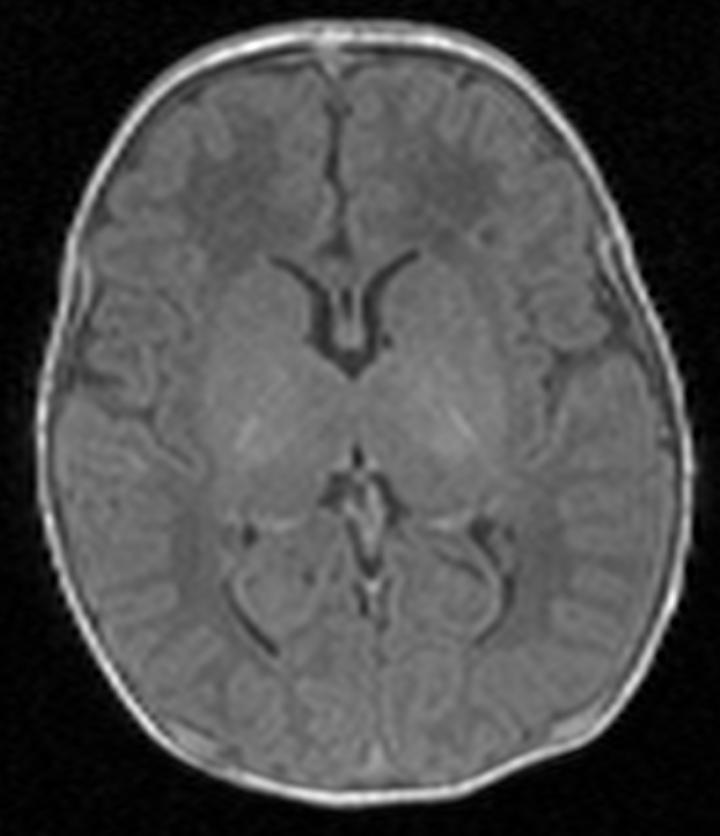

image: Scan one shows the brain of a healthy baby, while scan two shows that of a baby with brain damage. Compared to scan one, scan two shows abnormal brightness in the deep nuclei (in the centre of the brain), which indicates damage.

Any child suspected of having some type of damage is given an MRI scan shortly after birth. This allows doctors to look at black and white pictures of the brain see if any areas of the brain look lighter than others, as this may suggest damage. Doctors then use this information to give parents an estimation of the extent of the damage, and the possible long-term disabilities their child may face.